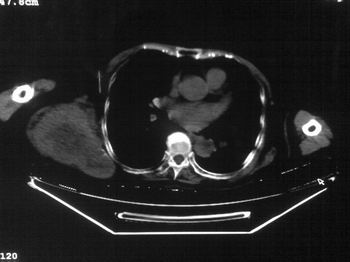

以下是引用dyqct在2007-9-11 16:52:00的发言:[br]支持右肩胛骨恶性肿瘤,性质不好定。

以下是引用zhangxu5888在2007-9-11 16:25:00的发言:[br]有侧肩胛骨溶骨性破坏且见软组织成分,增强软组织强化明显,中央见低密度坏死区!根据病史10年,考虑良性肿瘤恶性变!性质待定!

以下是引用老爱克斯新网客在2007-9-11 18:22:00的发言:[br]应该是良性肿瘤恶变,但因晚期破坏严重不能见到原来肿瘤征象无法判断,